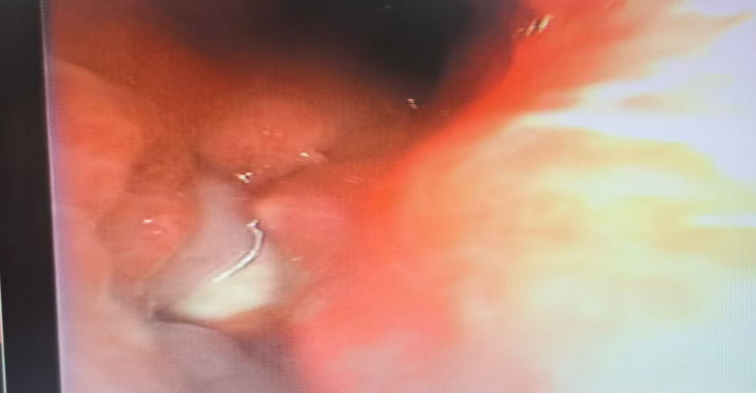

惊险案例:被肉芽包裹的花生

然而,情况远比想象中复杂和危险。这枚花生并非“安静”地待在气道里,而是在近一个月的“潜伏”中,引发了孩子身体的强烈排异反应——气道黏膜长出肉芽组织,将异物完全包裹。这不仅大大增加了取出难度,更导致了主气道的水肿和狭窄,严重威胁着孩子的呼吸。

这无疑是对医生技术的巨大考验。最终,凭借精湛的气管镜技术,医疗团队成功将这枚“惹祸”的花生完整取出,为孩子清除了这颗“定时炸弹”。目前,孩子正在顺利恢复中。